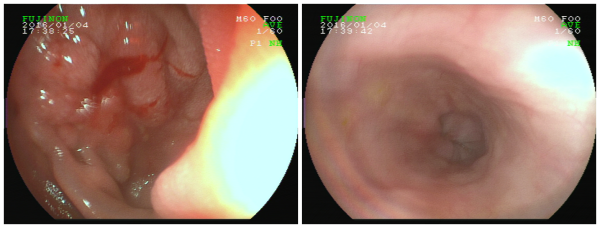

由于异物所在位置为十二指肠球降交界处,异物尖部已经插入小肠壁,若操作稍有不慎,异物尖部可能会划破肠壁及周围的脏器,引起肠穿孔或脏器大出血。在胃镜视野下,袁主任发现嵌在林先生患处的是一根包裹着食物残渣和胆汁的牙签!经过一个多小时细心谨慎的手术,一根约6.5cm的牙签被医生从林先生体内的十二指肠中取出,手术很顺利。术后,林先生便不再感觉腹痛,医生表示,再住院观察两天,林先生便可以出院了。

内镜视野下林先生体内的牙签

异物取出手术后